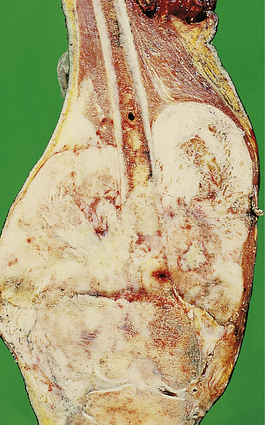

Fig. 25.10 Paget's disease. This affected femur shows characteristic thickening and deformity.

The most sinister complication of Paget's disease is osteosarcoma; the majority of elderly patients with osteosarcoma do have Paget's disease. As in younger patients, osteosarcoma develops in the long bones, particularly the humerus. The prognosis of osteosarcoma in Paget's disease is especially poor. There is also an increased incidence of other forms of sarcoma.

Patients with Paget's disease may also have heart failure. This is usually a simple coincidence of two common diseases of the elderly. However, the bone in patients with Paget's disease is extremely vascular (Fig. 25.9), and blood flow in these areas is markedly increased. This may represent an example of ‘high output heart failure’ (Ch. 13). Paget's disease is usually responsive to treatment with bisphosphonate drugs.